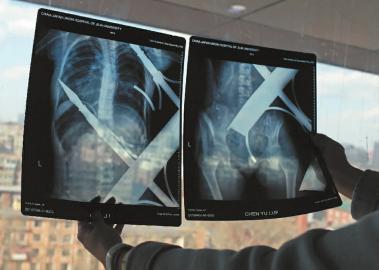

X光片顯示一根鋼筋將小女孩的右側(cè)肩膀刺穿,另外一根則從后背腰部以上靠近脊椎的地方穿入 白石 攝

在急診室的病床上,李紅旭看到了小雨?!八龗熘跗?,意識比較清醒。”進一步觀察,李紅旭一時說不出話來———一根鋼筋穿透小雨右側(cè)肩膀,另一根則從后背腰部以上靠近脊椎的地方穿入,從小雨左肩部分穿了出來。兩根鋼筋由兩根角鐵連接,距離事發(fā),小雨背著這片鐵柵欄已經(jīng)近7個小時了。